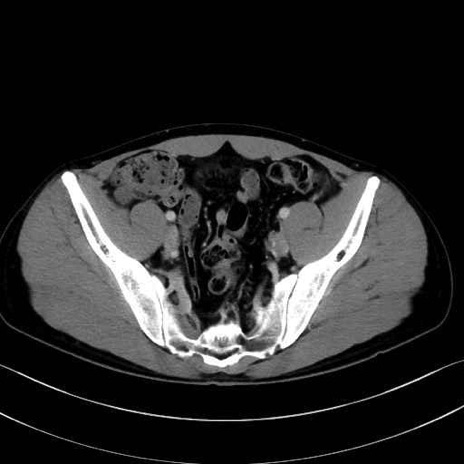

腸骨筋 (Iliacus)